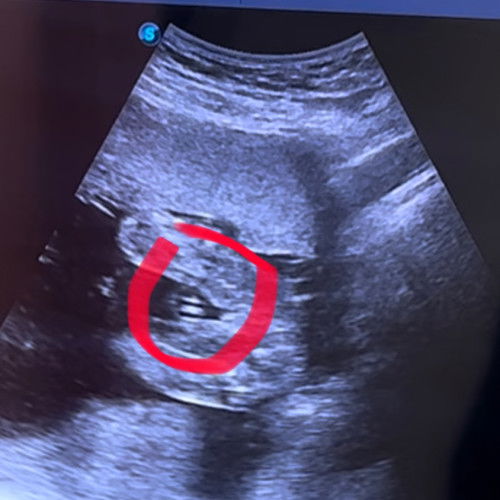

Hai mommies semoga sihat selalu . saya ada scan gender doktor kata baby girl . cuma nak comfirm dengan mommy pengalaman kalau mcm ni girl ke boy , risau sebab dah terbeli baju baby girl ni .. tq mommies sudi reply .. #firstbaby #ingintahu